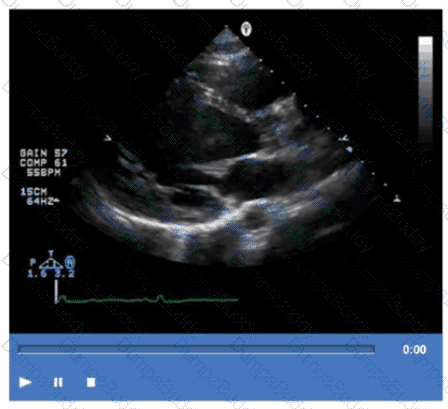

Which left ventricular regional wall segment is indicated by the arrow on this image?